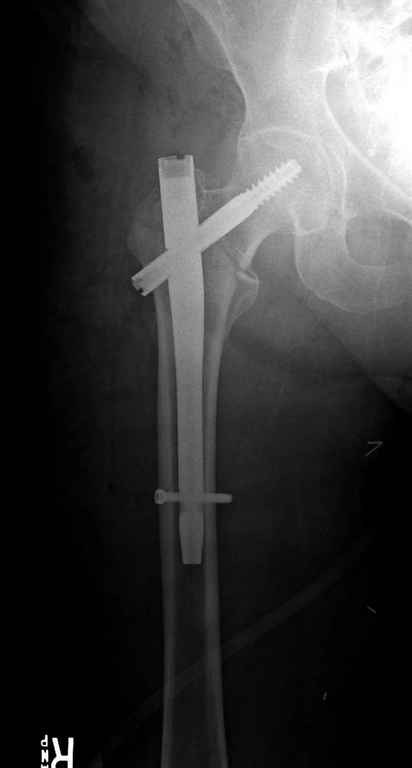

Перелом тут больше подвертельный. Нагрузка без торцевого упора на уровне перелома привела к телескопированию отломков на стержне. Ну и варус небольшой тоже свою лепту внес - если бы его не было, контактирующие латеральные стенки обоих отломков предотвратили бы укорочение, да и срослось бы за пару месяцев. А раз не срослось, упора отломков нет, более слабым местом оказались не нижние винты, а кость в головке и шейке. Так что надо было хотя бы удалить нижние винты до начала полной нагрузки.

На мой взгляд, причиной телескопирования явилось несоответствие диаметра гамма нэйл с диаметром канала подвертельного отдела бедра: обратите внимание на величину протрузии шеечного винта и величину медиализации дистального фрагмента - они одинаковы, смещение или телескопирование фрагментов происходило до того момента, пока гамма нэйл не упёрся в медиальный кортекс и образовалось пространство между латеральным

кортексом и латеральной поверхностью гвоздя.

В данном случае в головке бедра и в вертлужной впадине огромный дефект, навряд ли удалением импланта или заменой на другой можно сохранить сустав.

Здраствуйте. По данному снимку видно 2-а основных момента которые привели к протрузии винта в вертлужную впадину: 1) шеечный винт дистальной поверхностью наружнего края "зацепился" за латеральный кортикал бедра, это не дало сработать динамической системе гвоздь-винт. 2) лучьше шеечный винт проводить ближе к дуге Адамса, там болееплотная костная ткань. Решенее: как подготовка к эндопротезированию, реостеосинтез, можно такой же системой, но с учетом упомянутых моментов, максимальное безнагрузочное ЛФК (без боли).